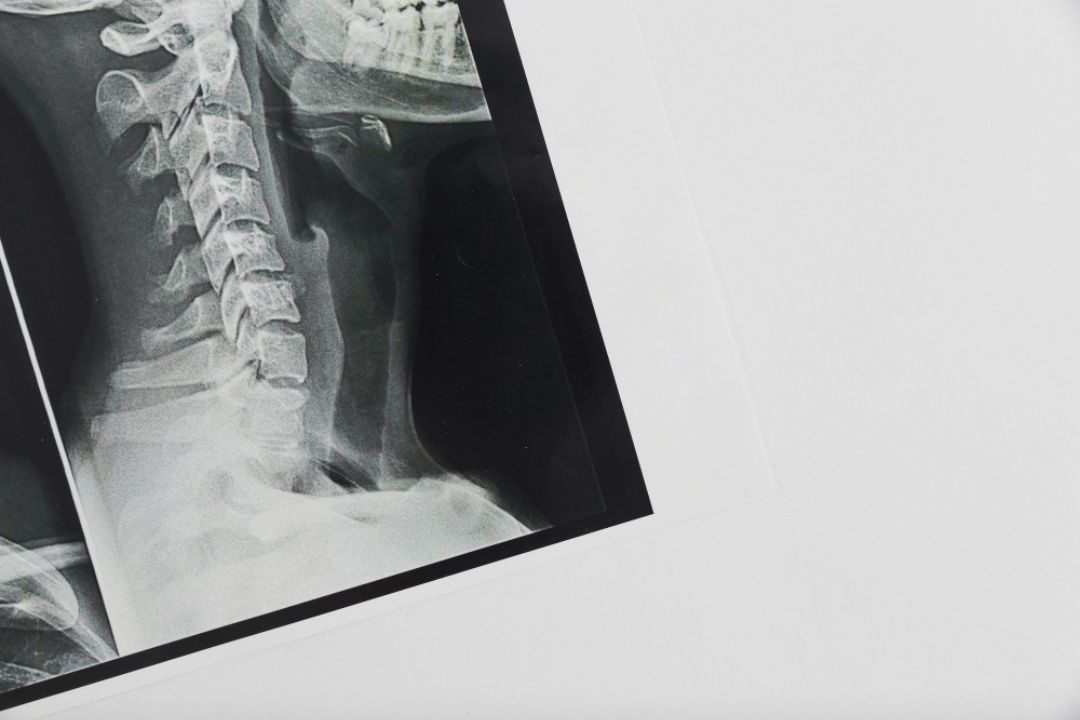

Lateral View X-ray is a specialized radiographic angle that captures the body part from the side rather than from the front or back. At Diagnopein, this imaging technique provides a detailed cross-sectional visualization of bones, joints, and soft tissues. It is commonly used for chest, spine, skull, and limb imaging where standard frontal projections may not reveal hidden details. Lateral View helps radiologists identify abnormalities, fractures, and pathologies that might otherwise go unnoticed in a single-plane X-ray.

Lateral View plays a vital role in diagnostic radiology by offering depth and dimensional understanding. For instance, in a chest X-ray, the lateral view helps distinguish lesions hidden behind the heart or diaphragm. In a spine X-ray, it allows doctors to evaluate the alignment of vertebral bodies and detect disc space narrowing, fractures, or spondylolisthesis.

This view is also useful for head, neck, and sinus evaluations, as it separates overlapping structures, giving a clearer view of bones and soft tissues. At Diagnopein, the Lateral View technique ensures diagnostic precision, supporting accurate clinical decisions and optimized treatment planning.